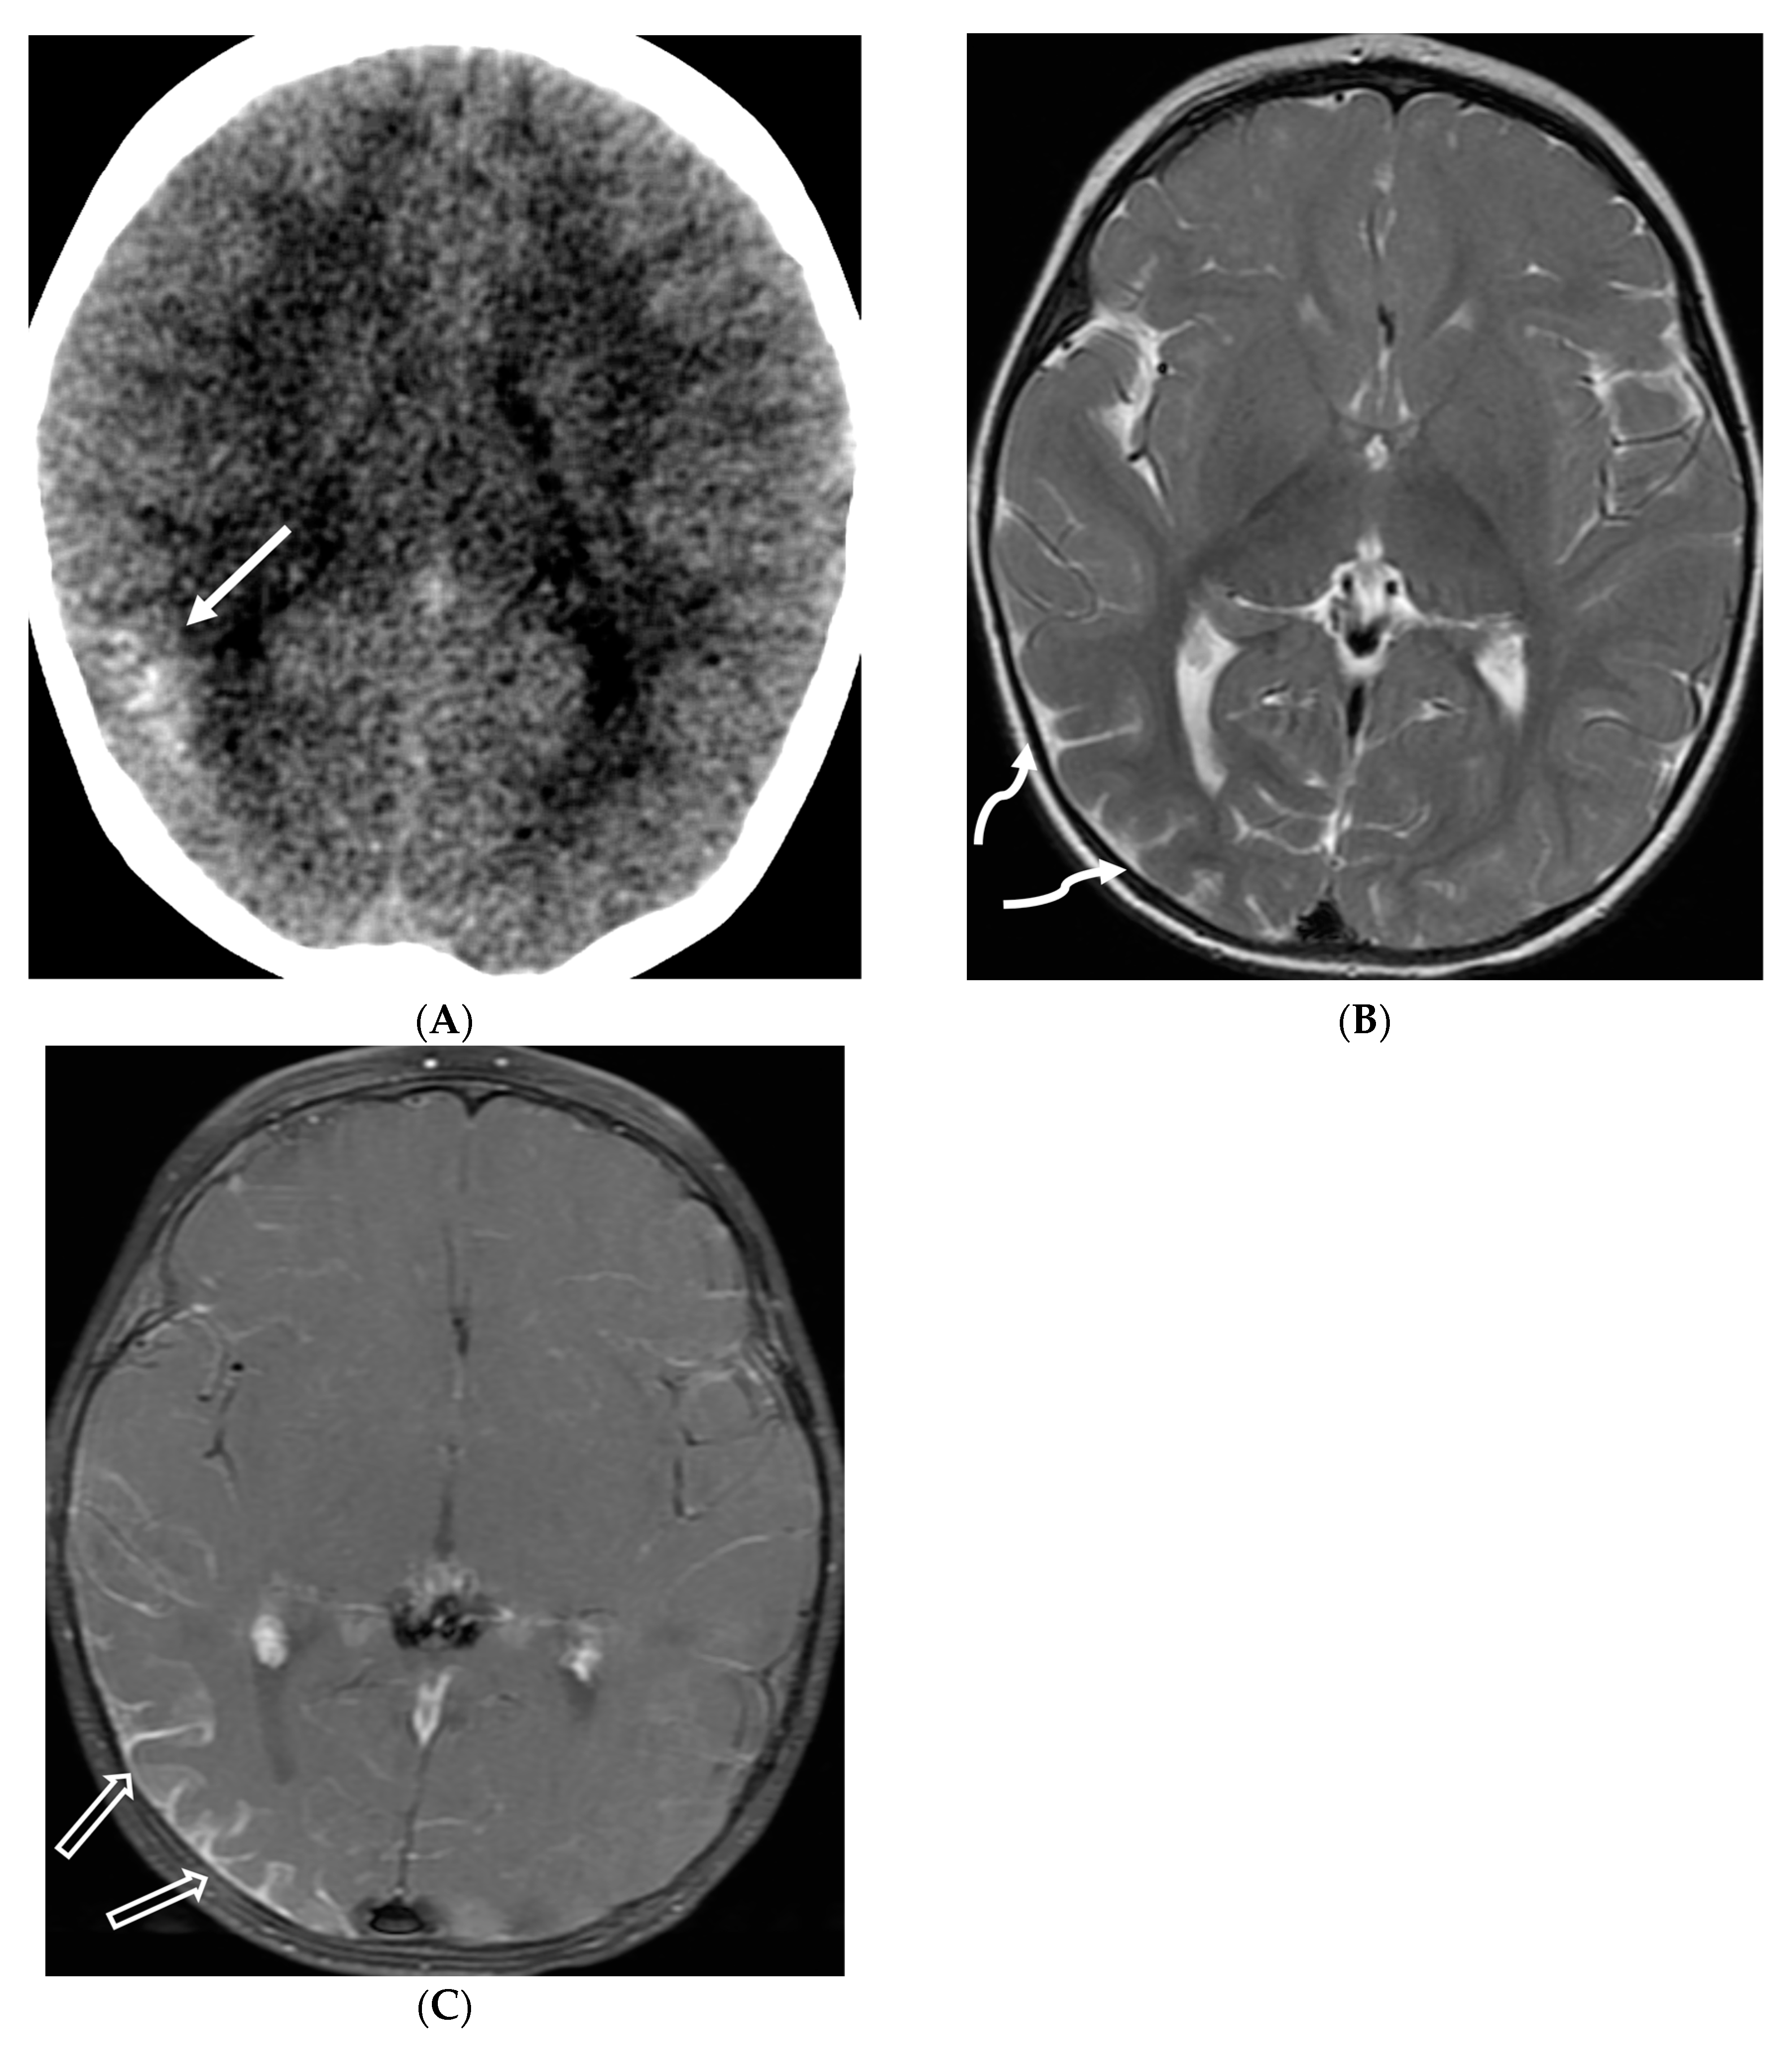

Figure 15.

Axial DWI (A), axial ADC (B), axial T1 FS post contrast (C) and Fluorodeoxyglucose Positron Emission Tomography (FDG–PET) scan (D): 13-year-old male with bilateral leg pains, headache, fever and weight loss: Blood tests and CT scan were concerning for Burkitt’s lymphoma. There is heterogeneous calvarial bone marrow signal with restricted diffusion (arrows) and patchy enhancement (curved arrows). Diffuse thickening and enhancement of pachymeninges in the supratentorial compartment is noted (dashed arrows). Findings are most consistent with lymphomatous involvement. Multifocal diffuse/heterogeneous pattern of FDG uptake within the axial and appendicular skeleton and the calvarium (open arrows). Intense FDG avid uptake is seen in the presacral mass (star).